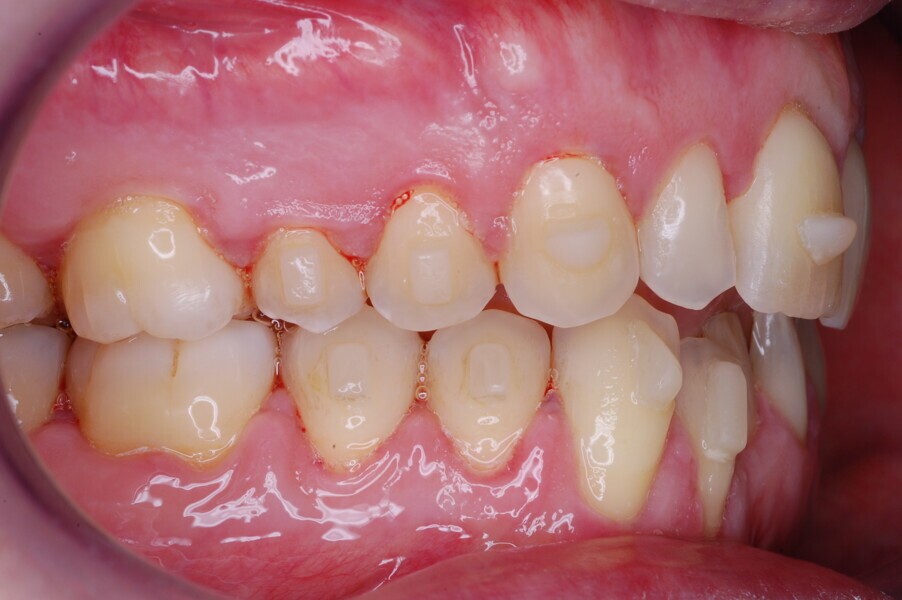

A healthy 39-year-old man presented to our orthodontic office with the chief complaint of an unattractive dental appearance and fear of the orthognathic surgery proposed by another orthodontist. Clinically, the patient’s profile was straight, and the frontal view did not show any facial asymmetry. The functional examination did not reveal any mandibular deviation or reduced movements. The patient had no joint pain, and no joint noise was observed.

Figs. 1–8: Pretreatment facial and intra-oral photographs.

From the periodontal point of view, the patient showed a good attitude to oral hygiene, but crowding of the mandibular incisors made cleaning difficult in that area, causing plaque accumulation and localised gingival inflammation. The panoramic radiograph revealed the presence of the mandibular third molars and confirmed the absence of the mandibular right central incisor (Fig. 10).

The cephalometric analysis showed a skeletal Class II malocclusion (convexity of Point A: 4.9 mm), a slightly retruded chin position (facial depth: 78.1°) and a skeletal open bite tendency (lower facial height: 53.19°; facial axis: 80.58°; Fig. 9). The mandibular incisors were lingually tipped (Li–APog: 9.3°) and retruded (Li–APog: 1.55 mm), and there was an increased inter-incisal angle of 142.9°.